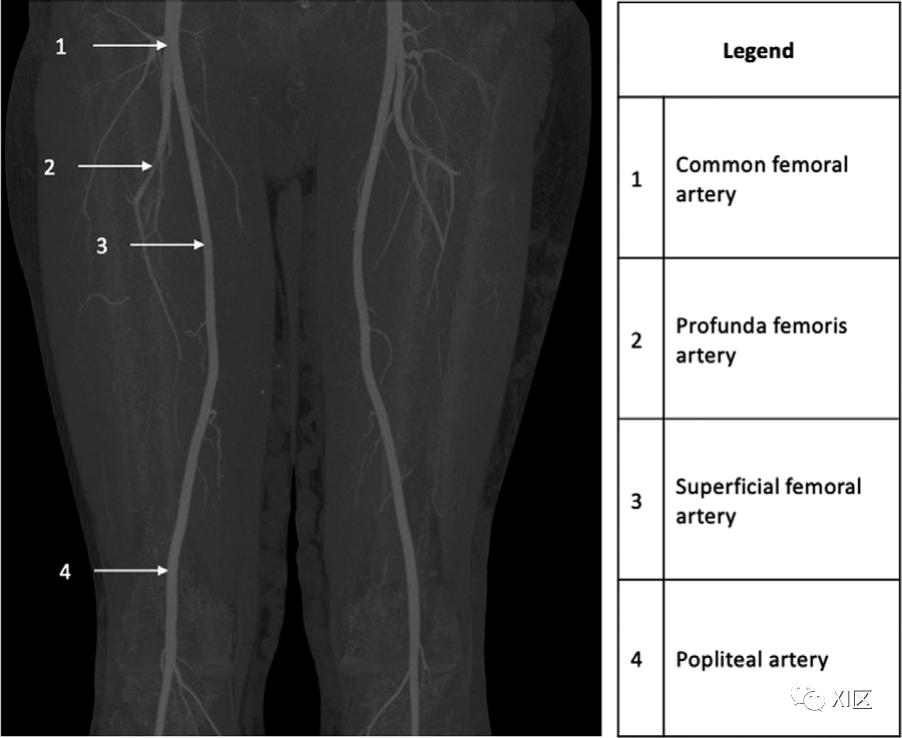

图1 35岁,解剖结构正常。冠状位上膝关节上方的最大密度投影CTA图像显示股总动脉(1)分叉成股浅动脉(3)和股深动脉(2)。股浅动脉与腘动脉相连(4)。当髂外动脉从腹股沟韧带下穿过,进入股三角区(大腿上部的解剖位置,以股四头肌、内收肌和腹股沟韧带为界),成为股总动脉(CFA)。定位CFA的血管标志是外侧髂周动脉和上腹下动脉。

CFA一般长4cm,直径为7.9-8.5mm,其主要分支股深动脉(PFA)和股浅动脉(SFA)构成了下肢的流出血管。CFA的最大分支是PFA,从外侧产生于腹股沟韧带远端3.5cm处。CFA分叉的水平对血管内介入有影响,特别是CFA的早期分叉使血管进入更困难。

PFA产生了有助于大腿内侧和后侧肌肉供应的穿支、供应大腿外侧部分的外侧环状动脉以及供应股骨头和股骨颈的股内侧环状动脉。40%的人存在PFA的分支模式和起源的变异,对这些变异的了解对动脉导管治疗和其他手术干预很重要。PFA的通畅性和位置很重要,因为在SFA疾病或闭塞的情况下,该血管通过旁路供应下肢。

在PFA之后,CFA的延续是SFA,其直径为6.0-6.3mm,在大腿前内侧的股四头肌和内收肌群之间延伸。虽然SFA很少表现出解剖学上的变异,但有0.025-0.04%的个体存在持续的坐骨神经伴行动脉。这发生在胚胎期的血管未能回流,仍然是下肢的主要供血血管,增加了动脉瘤和血栓栓塞并发症引起的肢体缺血的风险。穿过内收肌裂隙后,SFA成为腘动脉。内收肌裂隙是沿着内收肌的一个开口,代表了从大腿前部到腘窝的过渡点。